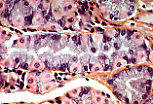

胃底腺的壁细胞(又称泌酸细胞/旁细胞)为锥体形,强嗜酸性,可分泌盐酸。胞质内大量线粒体与细胞膜内褶共同作用,是其呈现嗜酸性染色的原因。 |

肾上腺皮质细胞分泌类固醇激素,光镜下呈海绵细胞样。这类激素以胆固醇为原料合成,本身为脂质性;脂滴在组织制片过程中被提取,使细胞呈现海绵状外观。肾上腺皮质细胞的嗜酸性源于胞质内大量线粒体。 |

透射电镜下,合成皮质类固醇的特征性细胞器为管泡状嵴线粒体和滑面内质网。(本电镜照片仅展示线粒体。) |

甲状腺由滤泡(囊泡)构成。合成甲状腺激素的腺细胞高度随细胞活性变化:细胞相对不活跃时呈扁平状;合成前激素并分泌至滤泡中央腔时变为立方形;最终呈柱状时,会重吸收前激素、将其转化为活性激素并分泌至血管中。 |